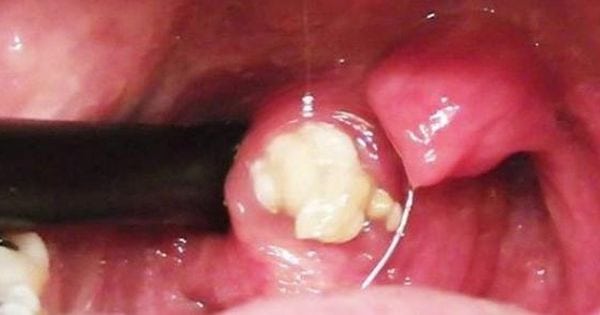

Soffrite di alito cattivo, raucedine e mal di gola? Questa potrebbe essere la causa!

Soffrite spesso di alito cattivo e mal di gola? Ecco quale potrebbe essere la causa. Se avvertite questi sintomi quali arrossamento, difficoltà di deglutizione, perdita del gusto e del dolore, presenza di piccole vesciche bianche potrebbe trattarsi di mughetto o candidosi orofaringea. Si tratta di un’infezione presente nella bocca o sulla lingua e compare quando … Leggi tutto